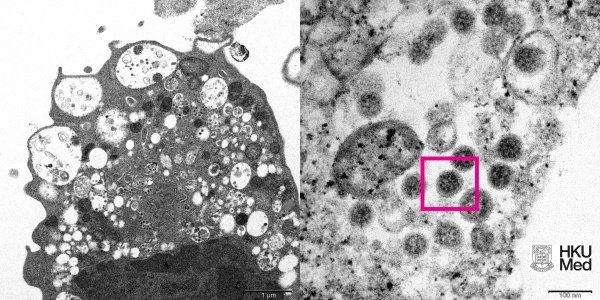

Хонконгийн их сургуулийн эрдэмтэд электрон микроскопын тусламжтайгаар коронавирусийн шинэ штамм болох омикроны зургийг авчээ. Улмаар энэ зургийг тус сургуулийн Твиттер хуудсанд нийтэлсэн байна.

Омикроны зургийг авахын тулд коронавирусийн энэ шинэ халдвар авсан сармагчны бөөрний эдийг эрдэмтэд авчээ. Ингээд гэрэл зургийг нэгийг нь багахан томруулж, нөгөөг нь хэд дахин томруулсан байдлаар гээд хоёр хувилбараар үзүүлсэн байна.

Томруулсан зурган дээр гадаргуу дээрээ титэм хэлбэртэй өргөсүүдтэй вирусийн хэсгүүд харагдаж байгаа аж.